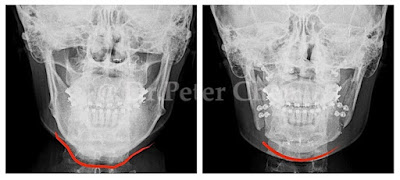

有些下顎骨突出的案例,從 X ray 上 會發現下顎骨前端(Menton)特別會突出一塊,

不笑時因軟組織包住較不明顯,笑的時候因為軟組織變薄了,骨骼的形狀就顯現出來,讓人有下巴多了一塊骨頭的錯覺。

在手術設計上,除了利用正顎手術將下顎骨退後,最好同時將下顎骨前端的骨骼重新雕塑,才能達到理想的效果。

療程效果因人而異,上圖為該案例實際術後成效